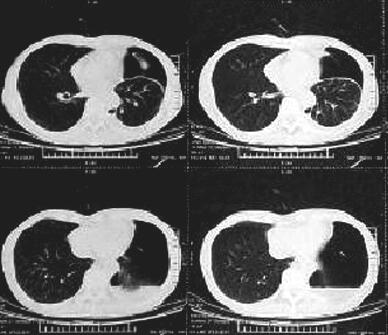

入院查体:形体消瘦,左肺叩诊呈浊音,听诊左肺呼吸音低。胸部彩超示:左侧胸腔大量积液(图1)。于入院后第2日行胸腔穿刺并细管引流术,当日共引流出约800ml血性浑浊液体。两次胸腔积液送细胞学:见癌细胞(腺型)。免疫组化:细胞角蛋白7(CK7)癌细胞(+)。血清肿瘤标志物(血还是胸腔积液?):细胞角质素19片段3.37ng/ml,糖类抗原72-4 9.03U/ml。引流3日后胸腔积液量<150ml/d,第4天引流袋内突发气泡溢出,呼吸困难加重,即刻行胸部CT示:左侧液气胸(引流术后),左肺部分萎陷、左侧胸膜增厚(图2)。该患者穿刺过程顺利,术后3日内,呼吸困难症状无反复,胸腔引流袋内未见气体逸出,第4天引流袋内突发气泡溢出,呼吸困难加重,提示穿刺操作失误造成气胸发生的可能性较小,而胸膜肿瘤灶脱落,形成癌性气胸的可能性较大。

图2 胸部CT(引流术后第3天)

左侧液气胸左肺部分萎陷,左侧胸膜增厚